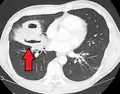

| Computed tomography (CT) scan of chest showing bilateral pneumonia with abscesses, effusions, and caverns. 37-year-old male. | |

Lung abscesses are often on one side and single involving posterior segments of the upper lobes and the apical segments of the lower lobes as these areas are gravity dependent when lying down. Presence of air-fluid levels implies rupture into the bronchial tree or rarely growth of gas forming organism.

Pulmonary abscess on CT scan -